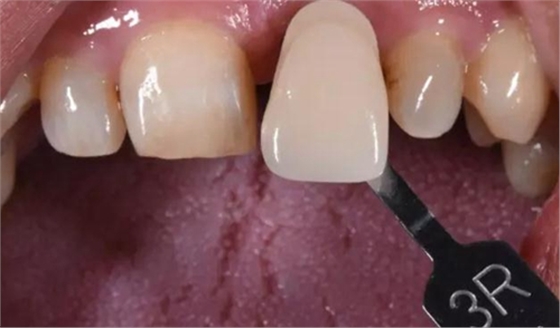

病例1:C先生,36歲,門牙外傷后拔除后3月。就診要求修復。

缺牙區(qū)比色照